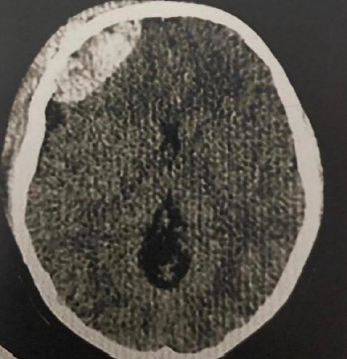

Uma criança de 8 anos de idade, vítima de trauma crânio encefálico, foi levado a um pronto atendimento de emergência pelo SAMU após queda de uma árvore de 4 metros. Deu entrada na emergência com Glasgow=13, tendo episódios de crise convulsiva, sendo tratado com medicação. Foi realizada uma tomografia de crânio que apresentou a imagem seguinte:

Diante do caso e da imagem acima, a conduta que o médico deve seguir é: